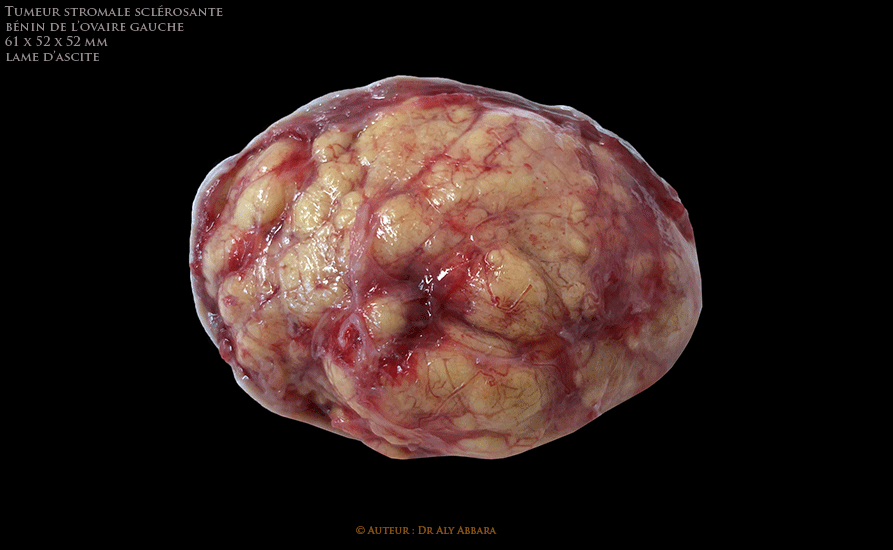

Tumeur ovarien gauche bénigne stromale sclérosante chez une adolescente de 16 ans - image clinique

L'exploration per-opératoire confirme qu'il s'agit d'une tumeur solide évoluant au dépens de l'ovaire gauche, sans végétations exophytiques ni implants péritonéaux, ni phénomène adhérentiel. Trompe utérine gauche, annexes utérines droites, utérus et le reste de l'exploration abdomino-pelvienne est sans particularité.

D'une tumeur ovarienne de 53 g (après fixation), d'aspect jaunâtre, mesurant 6 cm de grand axe, macroscopiquement homogène sans foyers de nécrose et sans hémorragie.

Histologiquement il s'agit d'une prolifération tumorale hétérogène présentant des territoires de haute densité cellulaire et pseudo-lobulaires (pseudo-nodulaires) séparés par des territoires paucicellulaires fibreux œdémateux ou myxoïde.

Les pseudo-nodules sont composés de cellules désorganisées fusiformes fibroblastiques ou arrondies au cytoplasme abondant et clair, vacuolé, au noyau rond ou ovalaire régulier, parfois nucléolé. Quelques cellules lutéinisées typiques sont présentes. D'autres cellules se caractérisent par leurs cytoplasme moins abondant éosinophile, avec noyau ovalaire et hyperchromatique.

Indice mitotique : 7 mitoses par 2 mm².

Présence d'un réseau vasculaire à paroi fine, parfois dilatés (aspect hémangiopéricytaire).